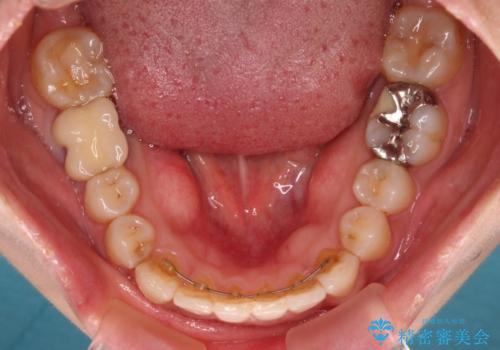

- 上下のクロスバイトと前歯のデコボコを気にして来院された患者様です。

骨格的に下顎がやや前方にあり、奥歯にクラウンが装着されているため、矯正治療後半の不安定な咬み合わせを避けるのであればワイヤー矯正がおすすめとなりますが、希望によりインビザラインにて治療を行うこととしました。

インビザラインを用い、IPR(歯と歯の間を削る)と歯列全体を拡大させることで、歯並びを整えていくこととしました。

懸念されたとおり、右下のクラウン部分が全く咬み合わず、仕上げの段階で治療期間が長くなりました。